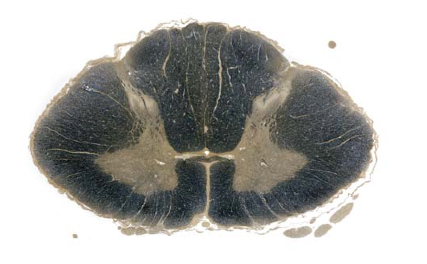

Thoracic spinal cord (myelin-stained); WM>GM